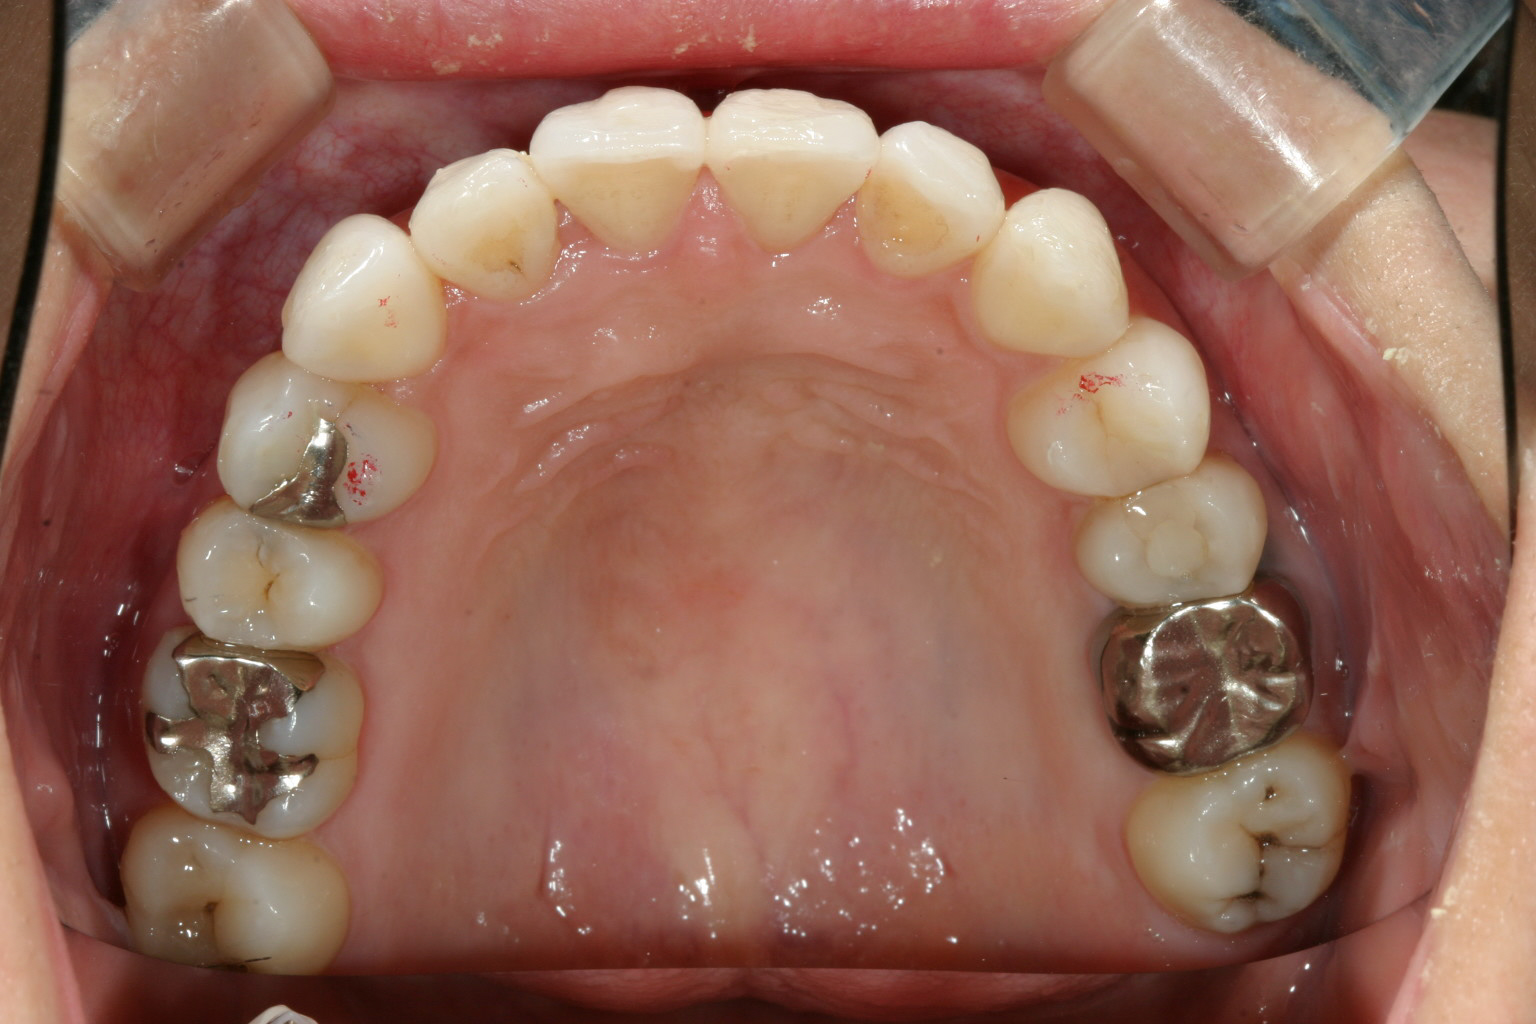

アーチを拡大し綺麗に改善しました。